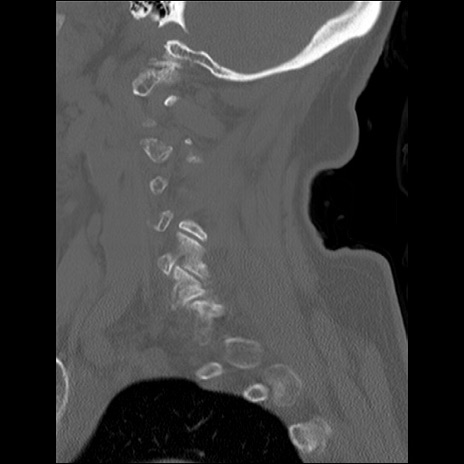

症例48 頚椎CT(矢状断像)

頚椎CT